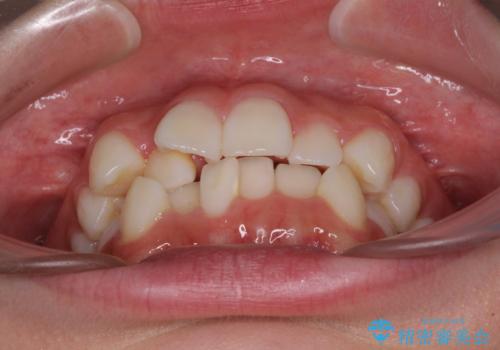

- 歯のデコボコや八重歯、クロスバイトを気にして来院された患者様です。

上下左右第一小臼歯4本を抜歯し、ワイヤー装置にて歯列を整え、さらには少しでも口元を引っ込めるよう矯正治療を行うこととしました。